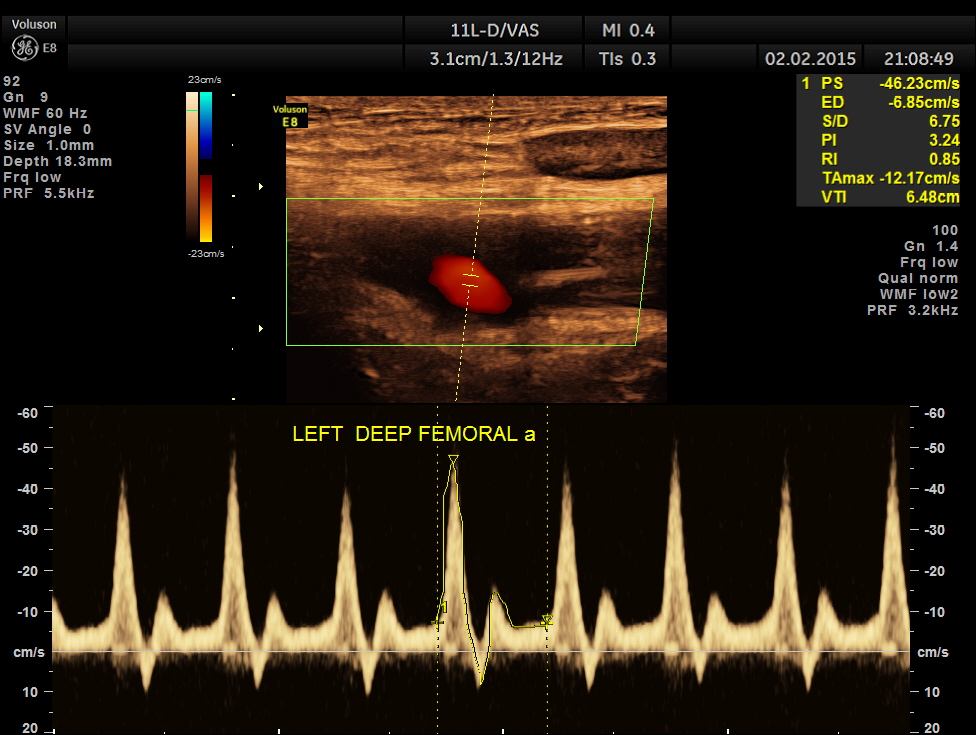

left profundal femoral artery shows normal flow